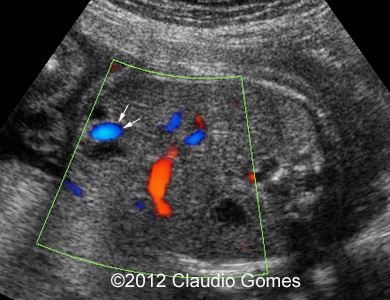

Image 1: At 21 weeks, persistent right umbilical vein ( arrow) next to gallbladder (*)

f1

Images 8-11: Persistent right umbilical vein and Inferior vena cava interruption with continuity of the flow via Azygos vein on grayscale and color Doppler

Fig8